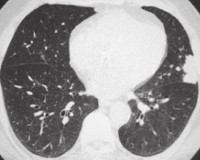

• Радиационная диагностика. При одиночном отростке на рентгенограмме легких визуализируются плотные округлые очаги. При диффузных поражениях дыхательных путей бронхолегочный рисунок улучшается, выявляется небольшое очаговое распространение. На плевральный амилоидоз указывают признаки гидроторакса - плотное затенение с косой линией Дамуасо в нижних отделах легких. КТ легких также выявляет увеличение средостенных лимфатических узлов.